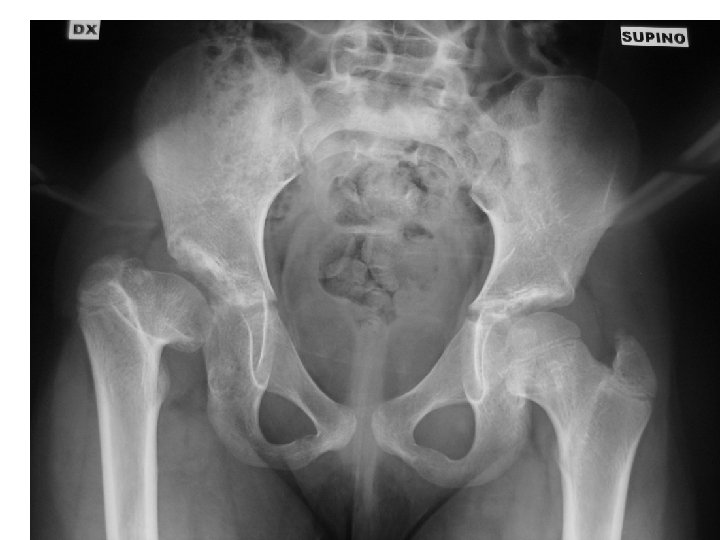

13 yo with hip pain, limp • Family has noted increased pain with activity, not able to walk long distances • No infantile treatment or history • Patient has features of Charcot-Marie. Tooth (associated with hip dysplasia)

• Bilateral periacetabular osteotomies • Bilateral femoral osteotomies